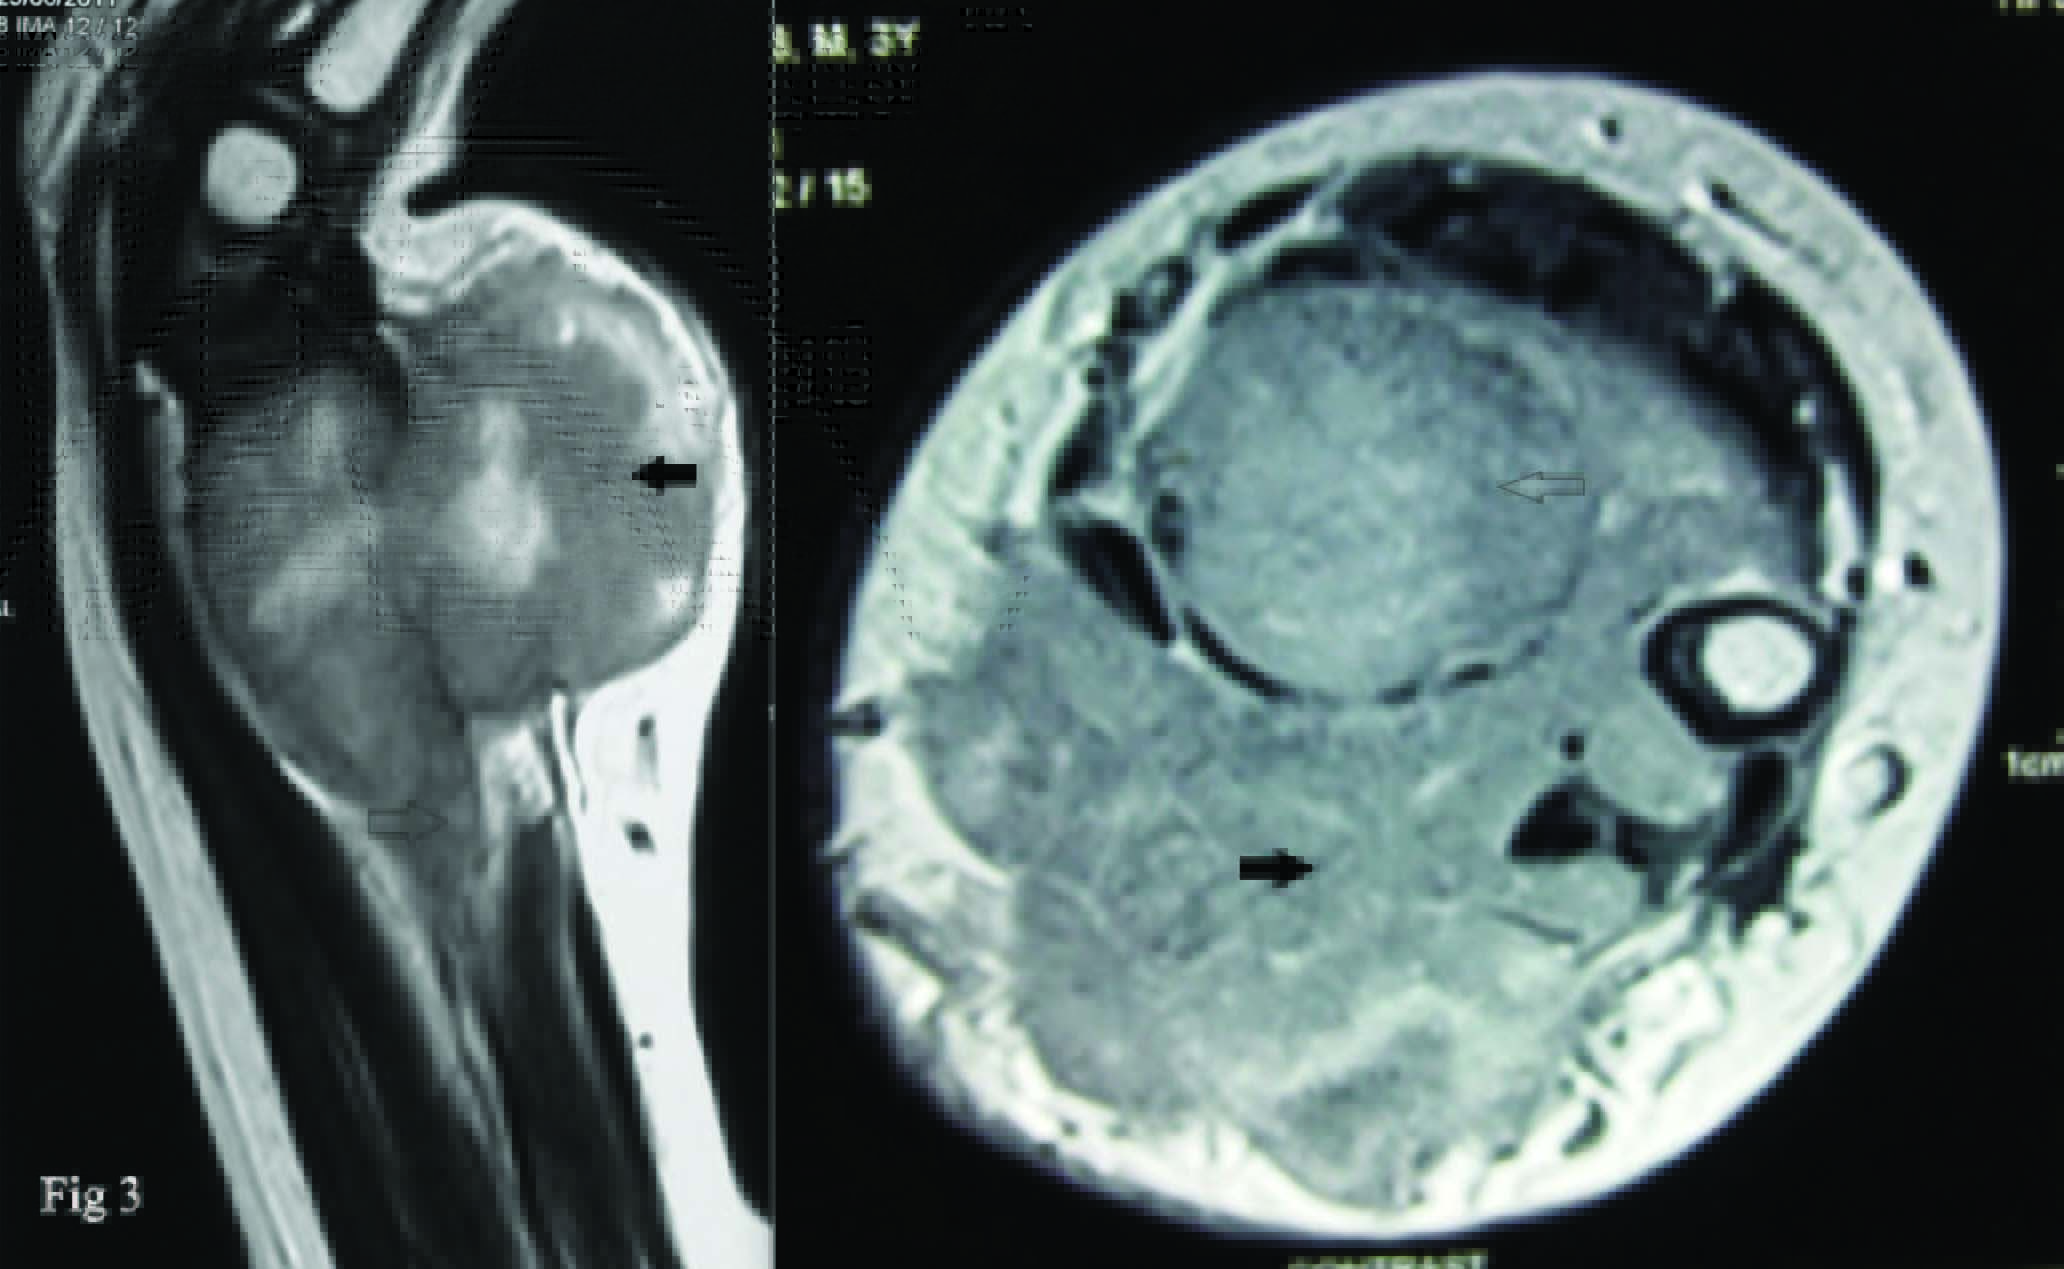

MRI revealed an aggressive predominantly solid lesion 4 x 3.6 x 2.8 cm, heterogenosly hypointense on T1 and T2 weighted images and hyperintense on STIR images [Table/Fig-3]. It was seen replacing the marrow cavity with a breach in anterior and posterior cortex and soft tissue extension. Proximal extent of lesion was 5.4 cm from distal articular surface of radius. The possible radiological differential diagnosis entertained were Chondroblastoma, Aneurysmal Bone Cyst, Osteosarcoma, Brown tumour of hyperparathyroidism and Giant cell tumour of bone. Normal serum alkaline phosphatase levels ruled out hyperparathyroidism. Core needle biopsy confirmed it to be a highly aggressive giant cell tumour (Enneking Stage III ) [Table/Fig-4]. Since it was a highly destructive lesion with destruction of cortex and a large soft tissue component, wide excision and reconstruction was performed. Postoperative specimen had tumour free margins on histopathology.

MRI demonstrating marrow spread (arrow) and soft tissue extent (solid arrow)